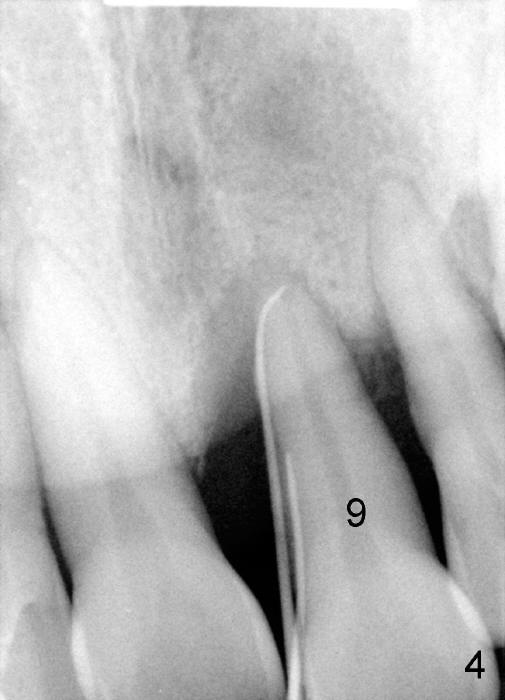

3. He has lost several upper teeth: #2,3,4,14 and 15.  The remaining teeth are loose, particularly #6,7, and 9 (Fig.1-4).  There are several treatment options for him.  Tell him that the doctor will discuss with him